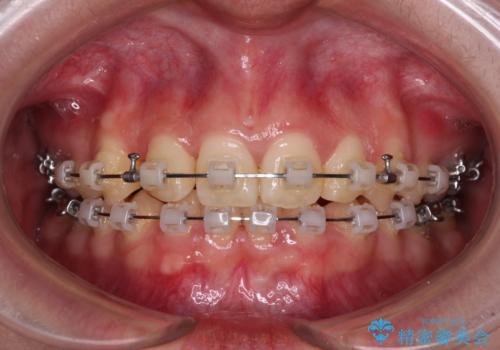

- 矯正装置

- クリアブラケット

上顎左右第一小臼歯2本を抜歯し、ワイヤー装置にて矯正治療を行うこととしました。